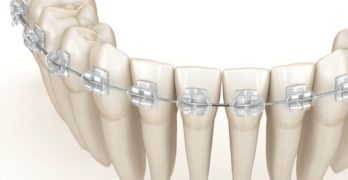

Revisión sobre los vances en los brackets para ortodoncia.

Comenzamos la semana con un artículo llamado Advancement in orthodontic brackets – Review y publicado recientemente en … [Leer más...] acerca de Revisión sobre los vances en los brackets para ortodoncia.